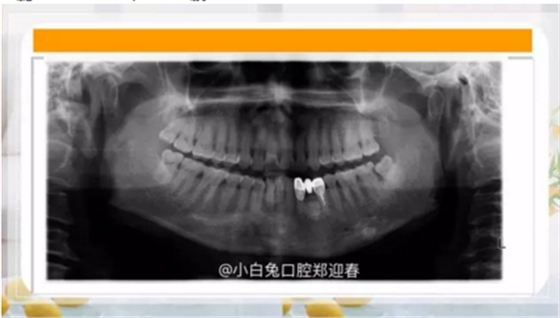

最近朋友圈轉(zhuǎn)發(fā)最多的一張片子,你知道嗎?

干脆潛到海底深處,猶如一艘核潛艇!

有路你不走,非要往前擠!

本是同兄弟,相煎何太急!

大魚(yú)吃小魚(yú)呢?還是再演一次9.11?